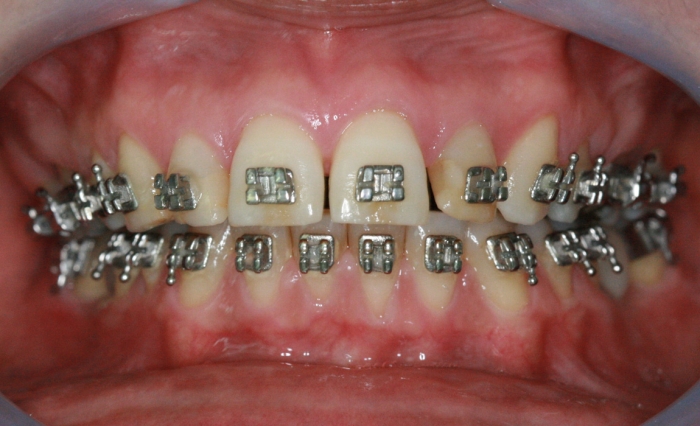

Mordida final